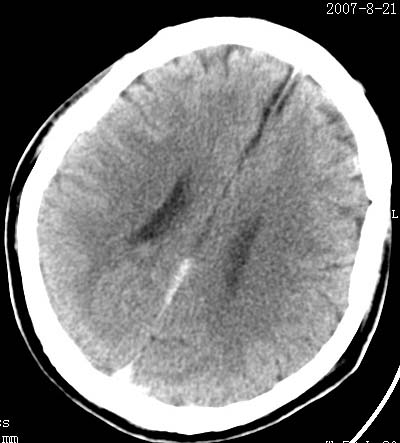

标题: CT9475:男性,38岁,与别人吵架后头痛/晕,恶性.呕吐入院. [打印本页]

标题: CT9475:男性,38岁,与别人吵架后头痛/晕,恶性.呕吐入院.

男性病人38岁,与别人吵架后头痛/晕,恶性.呕吐入院.请问大脑后纵裂是出血还是正常.

支持蛛网膜下腔少量出血

蛛网膜下腔少量出血

边缘比较模糊,考虑蛛网膜下腔出血哦。

大脑纵裂内少量蛛网膜下腔出血.

支持蛛网膜下腔少量出血,治疗后复查吧,但纵裂内的血吸收得很慢.

结合临床病史,考虑蛛网膜下腔出血可能,建议mr进一步检查或做一个cta(考虑动脉瘤)。

后纵裂密度增高,边缘模糊,结合病史考虑蛛网膜下腔可能,建议短期复查。病人因纠纷发病,诊断更要慎重!